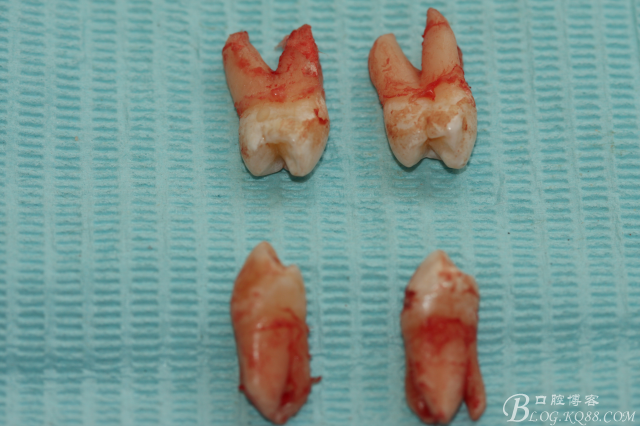

患者:江某某、男、14歲。因正畸治療需要拔除上下頜四顆第一前磨牙。按醫(yī)囑,局麻下拔除四顆第一前磨牙。牙齒拔除后發(fā)現(xiàn)四顆牙齒均為三個(gè)根,頰側(cè)兩根,腭側(cè)一個(gè)根。上頜第一前磨牙偶見三根。下頜第一前磨牙左右兩側(cè)均為三根,實(shí)屬罕見。發(fā)圖片,與同仁共勉。

手術(shù)圖片:

5.上頜離體第一前磨牙牙根形態(tài)

6.下頜離體第一前磨牙牙根形態(tài)

7.四顆離體上下頜第一前磨牙牙根形態(tài)